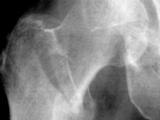

Fx-hip-intertrochanteric

Fx-hip-intertrochanteric